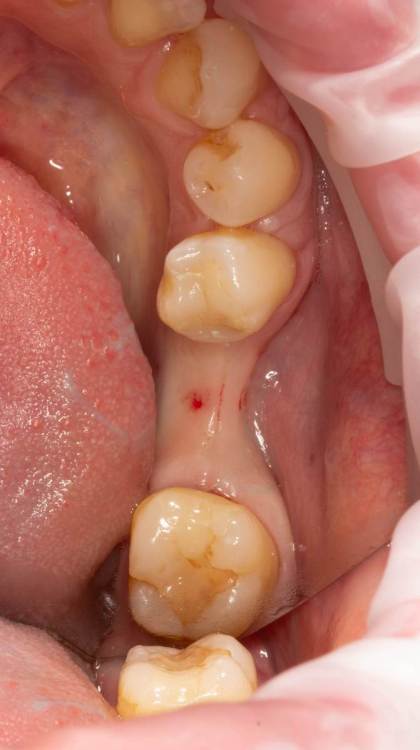

Женька Опубликовано 19 июня, 2023 Поделиться Опубликовано 19 июня, 2023 Здравствуйте, коллеги. Примерно с нового года начал ставить ТЛ имплантаты Дентиум. Что-то под заглушку (не поймал торки, представляете?). Что-то на низких формирвателях. И вот пришла пора протезирования, но отпустить к ортопеду не подготовив десну - не получается. Создал сам себе проблем, сегодня вот исправлял. Получилось неплохо? 3 Ссылка на комментарий